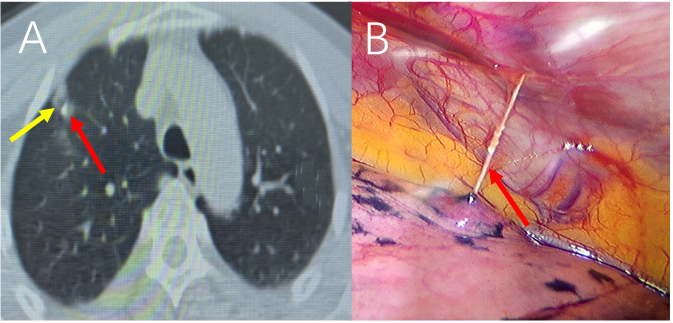

图A:黄色箭头代表GGN,红色箭头代表定位钩;图B:箭头所示定位线。

胸外科姜建涛主任医师带领团队成员孔冉冉副主任医师、李建忠副研究员和郭询医师在放疗科CT定位室潘继元技师的大力支持下,连续完成5例CT引导下多钩固定、实时释放锁定病变部位肺穿刺定位术。患者穿刺定位后可正常活动,疼痛感较传统定位明显减轻。术者可选手术时间自由(24h内),不影响手术安排,术中轻轻提取定位线暴露病变部位,方便手术操作,明显缩短手术时间,降低了围手术期并发症发生率。经过医护人员精心的治疗、护理,术后第1天患者下床活动,术后3天出院。